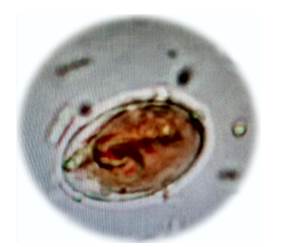

Las heces evaluadas fueron sometidas a escala cualitativa de evaluación de la presencia de trofozoitos y quistes de Giardia duodenalis, bajo la metodología de cruces, dando valores de 0 (Sin presencia), 1 (Baja), 2 (Moderada), 3 (Alta), (Figura 1 y Figura 2).

De los 112 coprológicos realizados, se encontró que 60 (55%) presentaron parásitos gastrointestinales de los cuales solo 10 (8.9%), presentaron formas de G. duodenalis, en las heces y correspondiendo este tipo de parásito solo al 16,6% de la parasitosis total, en cuanto a la presencia de cruces de los animales parasitados, con 1 (una cruz) dos caninos (20%), para 2 (dos cruces) cinco caninos (50%) y con 3 (tres cruces), tres ejemplares (30%), mientras que para la presencia de las formas reproductivas del parasito, se estableció, que para los trofozoítos, los hallazgos mostraron que tres coprológicos, tenían 1 cruz, cuatro muestras mostraron 2 cruces y cinco caninos tuvieron 3 cruces respectivamente, mientras que la presencia de quistes, la relación fue para 1 cruz dos caninos, 2 cruces, seis caninos y para 3 cruces, dos muestras.